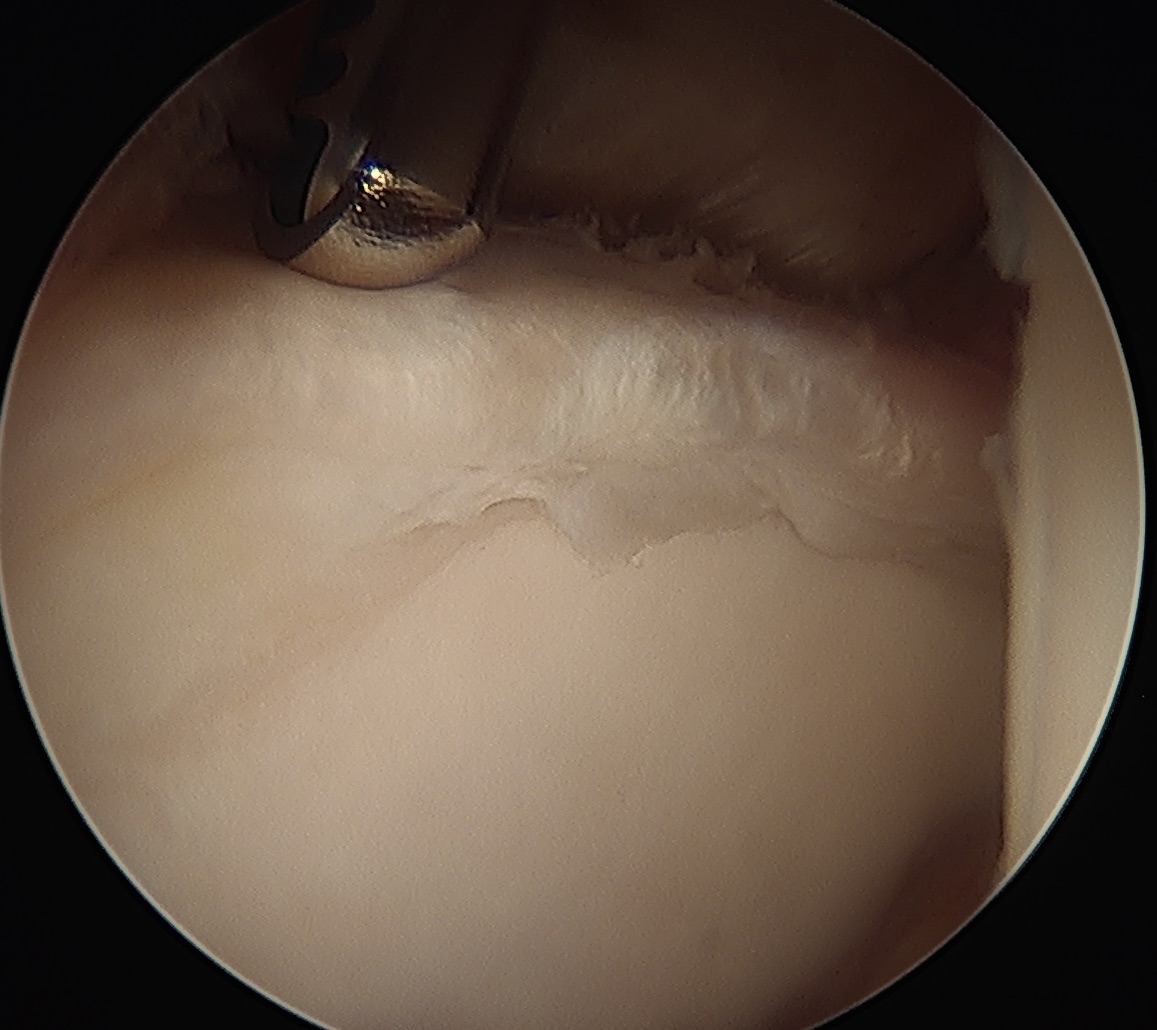

During this keyhole procedure, anchors with sutures are used to repair the labral tear. Extra bone is taken away from the acetabulum and the femoral head / neck area as needed. Usually the hip capsule is opened to access the hip joint fully, and this is carefully closed at the end of surgery.

Potential causes of ongoing pain include labral re-tear, ongoing bony impingement, cartilage damage, capsular adhesions and capsular tears or defects.